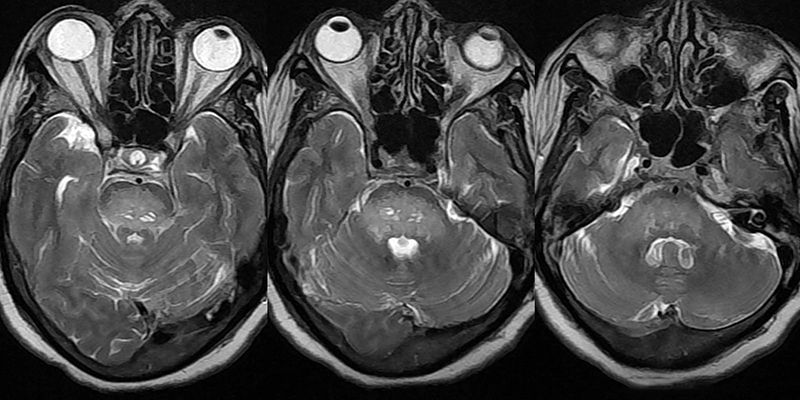

- И наконец, МРТ глаза, которое проводится с целью выявить нарушения со стороны всех тканей глаза.